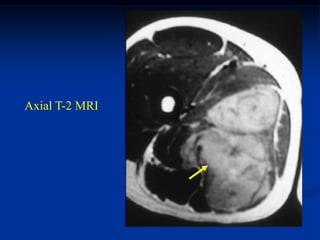

Case #259.2                   MFH with skip lesions

64 year male with painful soft tissue mass in thigh for 6 mos

Cor STIR   Ant STIR   Gad

Axial T-2   Lower T-2

Lower Gad

Sag Gad   Gad